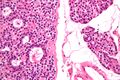

صورة مجهرية لغدوم الجار درقية (يسار) وغدة جارات درقية طبيعية (يمين). صبغة الهيماتوكسيلين واليوزين.

يتم تأكيد فرط نشاط جارات الدرقية عن طريق اختبارات الدم مثل مستويات الكالسيوم وهرمون الغدة الدرقية. اختبار محدد لغدوم الجار درقية هو التصوير الومضاني لغدة الجار درقية سيستاميبي. تكشف تقنية التصوير النووي هذه عن وجود وموقع أنسجة جارات الدرقية المرضية.[7]